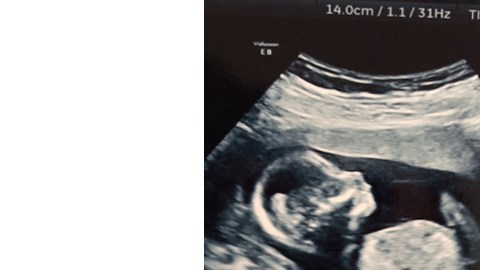

El ultrasonido compartido por la pareja en JustGiving. Crédito: Justgiving.com

Todo marchaba bien hasta que la pareja asistió al ultrasonido correspondiente en la semana 20 de gestación, cuando el personal médico les informó que algo estaba mal con su hija.